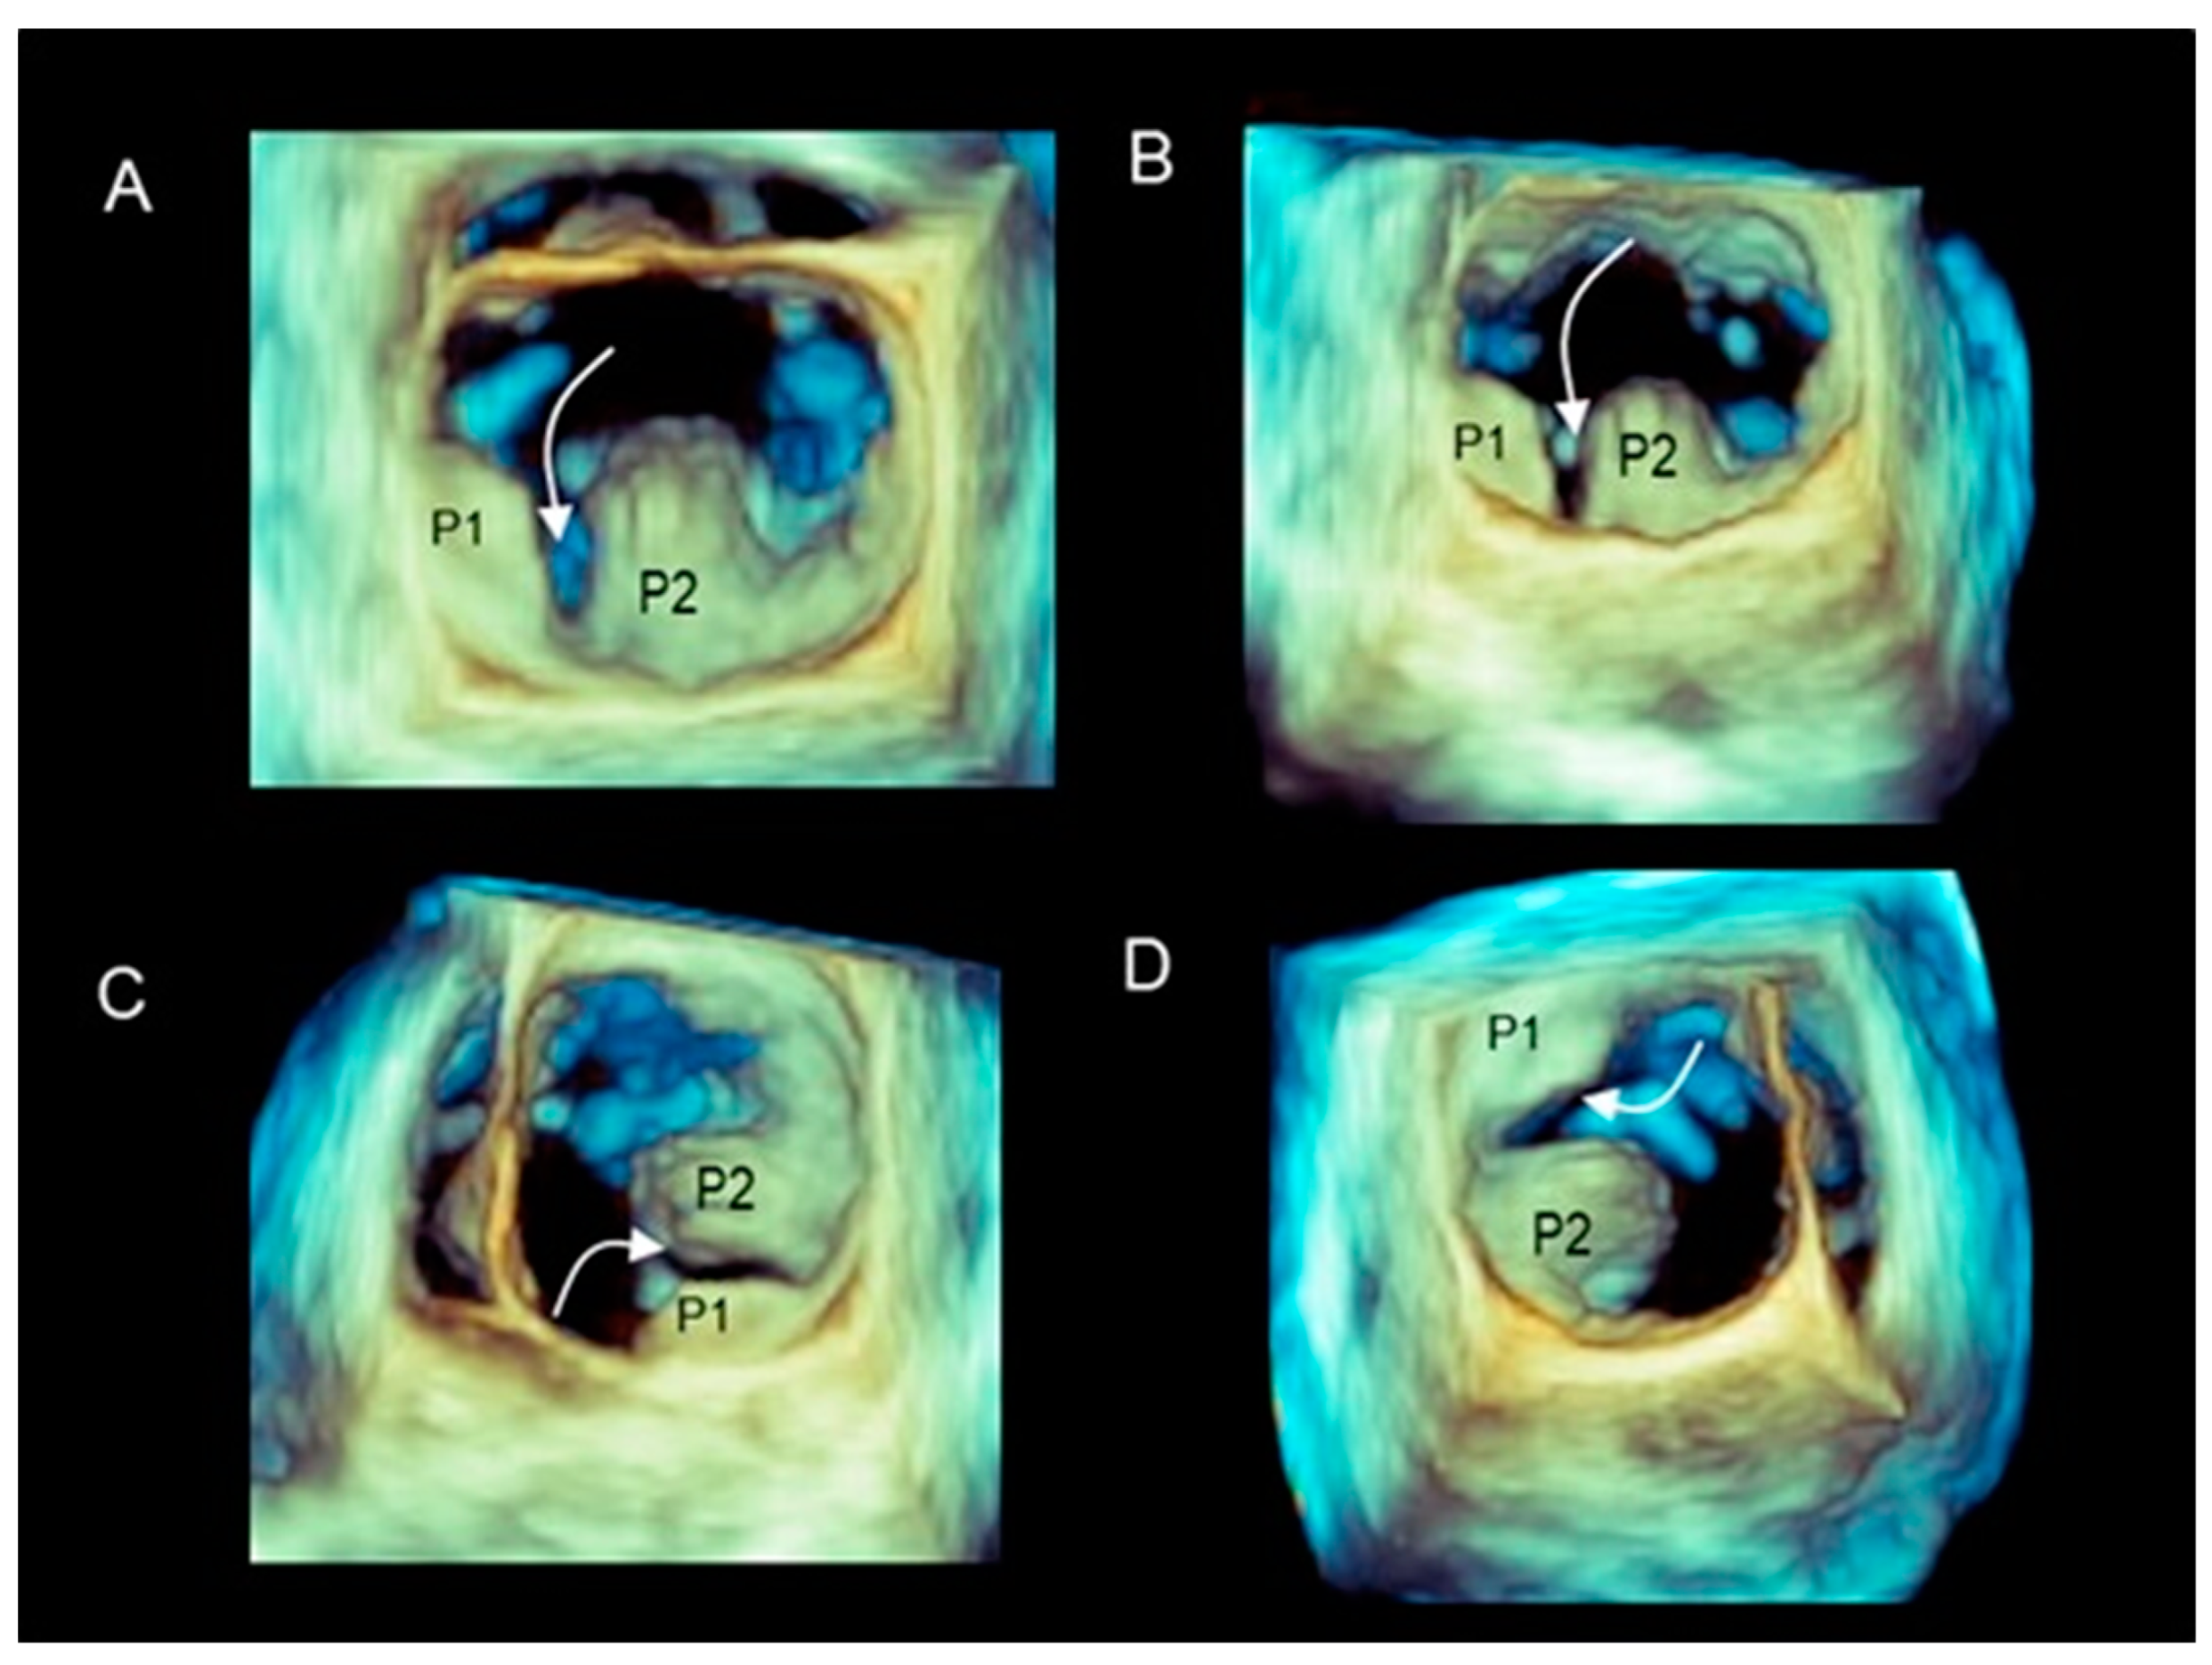

2.4. Scenario # 4

Different Shapes of P2 Prolapse, Partial Prolapse, and Commissural Prolapse